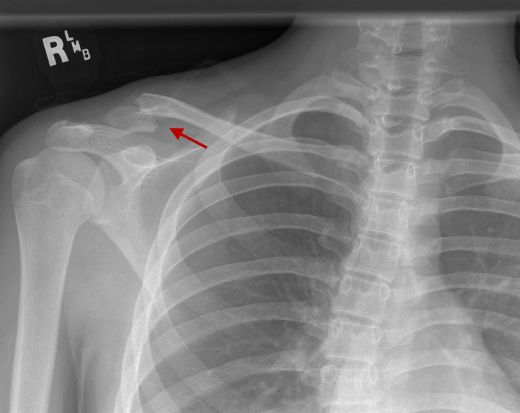

Eklem bölgelerinde meydana gelen yaralanmalar ve travmalar, kemik dokusunun hasar görmesine ve onarım sürecinde osteofitlerin oluşmasına yol açabilir. Özellikle sporcularda sıkça görülen bu durum, eklemdeki kıkırdağın zedelenmesiyle ilişkili olarak ortaya çıkar.

Kemik çıkıntısı, tıbbi literatürde "osteofit" olarak adlandırılan, kemik dokusunun anormal büyümesi sonucu oluşan bir yapıdır. Genellikle eklem bölgelerinde meydana gelir ve bu durum çeşitli sağlık sorunlarıyla ilişkilidir. Kemik çıkıntılarının oluşumunu etkileyen birçok sebep bulunmaktadır. Bu makalede, kemik çıkıntısının nedenleri, risk faktörleri ve tedavi yöntemleri üzerinde durulacaktır.